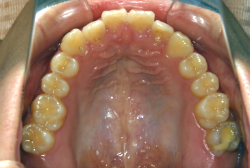

成長発育期の叢生症例・非抜歯治療

今回は「歯並びの凸凹を治したい」という主訴で来院したケースです。診断の結果、「成長発育期の叢生」と判明しました。叢生とは歯並びの凸凹のことですが、この方の場合は上顎が少々重症で、上の犬歯が外側へ飛び出し、いわゆる「八重歯」という状態でした。凸凹の解消のためには永久歯を抜歯して隙間を作って残った歯をきれいに配列する方法(抜歯法)と、歯列を拡大して配列する方法(非抜歯法)の2種類があります。歯列の拡大にはさらに2つの方法が有り、横方向へ拡大する場合と、臼歯を後方に移動させて拡大する方法があります。今回の症例のようなケースでは、横方向へ拡大してもあまり効果的ではなく、後方への移動が最適です。上の臼歯を後方へ移動させるために、今回はヘッドギヤという取り外し式の装置を、夜寝る時に半年ほど使用していただきました。

この方の場合、治療期間はヘッドギアを6ヶ月、マルチブラケット法を7ヶ月でした。治療後は凸凹が改善しただけでなく唇の審美性が大幅に改善しました。もちろん噛み合わせ的にも正しい状態が確立しています。